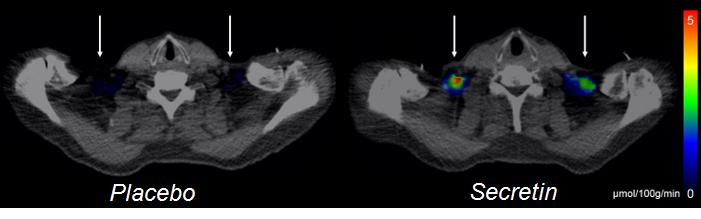

Positron emission tomography images showing glucose tracer uptake after placebo and secretin infusions

Positron emission tomography images showing glucose tracer uptake after placebo and secretin infusions. Arrows show the location of brown adipose tissue.

– Secretin is a hormone secreted into blood circulation by the intestines, and it stimulates the production of peptic juices in the pancreas when we have meals. In our research, we discovered secretin receptors in the brown adipose tissue of healthy people, which suggested that secretin also affects brown fat. Secretin infusions not only increased glucose uptake in brown adipose tissue, but also elevated energy expenditure in the whole body, says Doctoral Candidate, Cardiologist Sanna Laurila from the University of Turku.